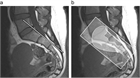

1. 診断および疾患活動性評価のための仙腸関節MRIの撮影条件について、ASAS-SPARTANによる推奨に沿ったものとした。